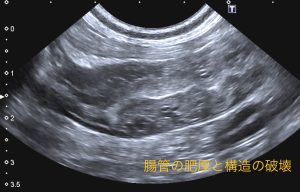

こんにちは。獣医師の永井です。 今回は肉芽腫性腸炎についてです。 肉芽腫性腸炎は、稀な疾患であり、回腸と大腸に…]]>

こんにちは。獣医師の永井です。 今回は肉芽腫性腸炎についてです。 肉芽腫性腸炎は、稀な疾患であり、回腸と大腸に…]]>